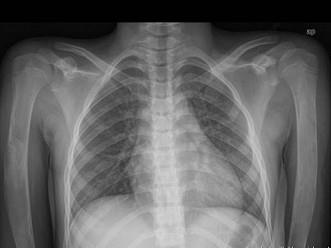

问题 女,12岁,脊柱侧弯畸形,双下肢长短不一,请结合影像图像,最可能的诊断是 ( )

选项 A、非骨化性纤维瘤 B、Paget病 C、骨巨细胞瘤 D、内生软骨瘤 E、骨纤维异常增殖症

答案 E